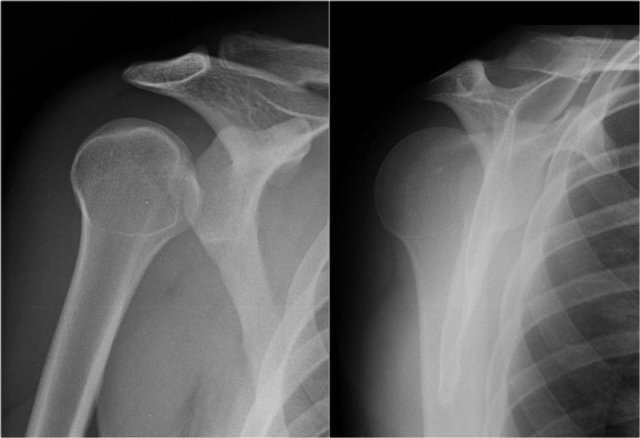

Posterior dislocation

Posterior dislocations are uncommon and easily missed, because there is less displacement compared to the anterior dislocation.

On the AP-view the head looks strange due to the internal rotation.

On the transscapular-Y view the humeral head is displaced posteriorly.

Sometimes the displacement is difficult to appreciate, especially when the transscapular-Y view is slightly rotated.

Sometimes an axillary view can be of help, but when in doubt go to CT.

Images of another patient with a posterior dislocation.

Notice the distance between the humeral head and the glenoid on the AP-view, which is abnormally wide.

Posterior dislocations are uncommon and not as obvious on the X-rays as an anterior dislocation.

Approximately half of the posterior shoulder dislocations go undiagnosed on initial presentation, because of a low level of clinical suspicion and insufficient imaging.

Posterior dislocations account for 2-4% of all shoulder dislocations.

Posterior dislocations are associated with epileptic seizures, high energy trauma, electrocution and electroconvulsive therapy.

On the images a posterior dislocation is seen with a fracture.